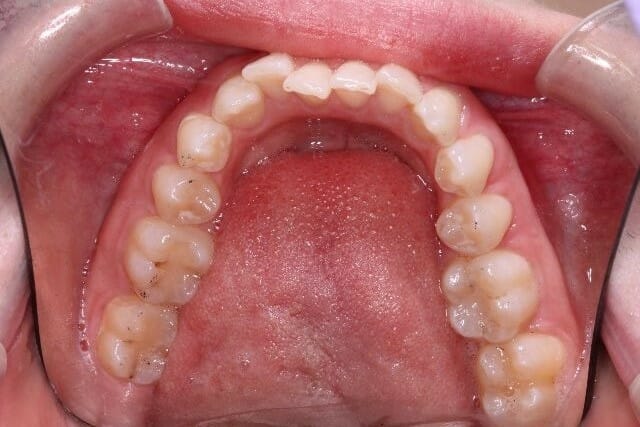

Crown & Veneer

Before